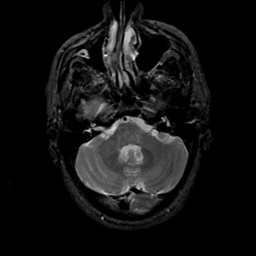

MR Study #21, November 3, 1991 -- Slice #11